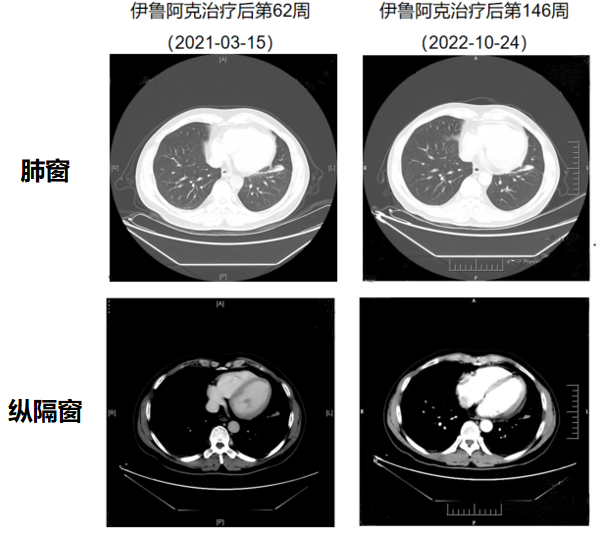

近年来,各种间变性淋巴瘤激酶(ALK)抑制剂层出不穷,ALK阳性晚期非小细胞肺癌(NSCLC)的治疗领域呈现百花齐放的格局,如何优化治疗策略成为临床热点问题之一。为拓宽ALK阳性NSCLC的治疗视角,中国医学论坛报联合齐鲁制药开展“实例呈现——最佳临床ALK阳性NSCLC病例分享”专栏,以期为广大临床医生提供实用的专业经验及诊疗参考。 2023年6月28日,国家药品监督管理局批准伊鲁阿克片(商品名:启欣可®)上市,为ALK阳性的非小细胞肺癌患者提供了新的治疗选择。 第二期特约安徽省肿瘤医院田田医生分享病例《一例ALK阳性NSCLC患者经克唑替尼治疗失败后接受伊鲁阿克治疗长达33.7个月》,特邀安徽省肿瘤医院张志红教授担任点评嘉宾。现将病例及点评内容整理如下,供大家分享、交流。 1. 该患者为41岁男性,ECOG:0分;2017年10月27日首次确诊为肺腺癌,伴淋巴结转移、胸膜转移、胸腔积液、心包积液; 2. 2017年11月开始克唑替尼治疗,2019年11月疗效评价达PD标准,提示克唑替尼耐药,2019年11月14日予以血管内皮抑制素联合卡铂治疗1个疗程,2019年12月26日结束克唑替尼治疗,克唑替尼治疗总时长为25个月; 一般资料:患者男性,汉族,41岁。身高:170cm,体重:75kg,ECOG:0分。 诊断:2017年10月27 日首次确诊为肺腺癌,伴淋巴结转移、胸膜转移、胸腔积液、心包积液。 图1-1 患者治疗经过 第一阶段:克唑替尼治疗 治疗方案:2017年11月开始给予克唑替尼治疗。2019年11月14日,给予血管内皮抑制素联合卡铂治疗1个疗程。 疗效评价及辅助检查:克唑替尼治疗2年后(2019年11月11日),患者胸膜病灶增大、胸腔渗出液增多,疗效评价达到疾病进展(PD)标准,提示克唑替尼耐药。 2019年12月9日病理诊断结果(图2-1):(左侧胸膜)纤维脂肪组织内见少许异型细胞,组织甚少,结合免疫组化标记结果,符合腺癌。 2019年12月16日FISH检测纤支镜活检组织样本结果为ALK 阳性(图2-2)。 2019年12月26日结束克唑替尼治疗,最佳总缓解为疾病稳定(SD),克唑替尼治疗总时长为25个月。 图2-1 克唑替尼耐药后的组织病理检查结果 图2-2 克唑替尼耐药后的分子病理检查结果 第二阶段:伊鲁阿克治疗 治疗方案:2020年1月3日,患者接受伊鲁阿克60mg QD治疗7天,第8天起顺利上调剂量至180mg QD,此后维持该剂量。 疗效评价及辅助检查:2022年10月24日,2组淋巴结(气管旁)增大、心包积液增多,提示影像学进展(图3-1至图3-5)。2022年10月24日终止伊鲁阿克治疗。用药后第6周首次评价为部分缓解(PR),且持续至用药后第135周,最佳总缓解为PR。 图3-1 伊鲁阿克治疗期间胸部CT 图3-2 伊鲁阿克治疗期间胸部CT 图3-3 伊鲁阿克治疗期间淋巴结影像学 图3-4 伊鲁阿克治疗期间淋巴结影像学 安全性:接受伊鲁阿克治疗期间耐受性良好,大多数不良事件(AE)为1级(图3-5),无SAE发生,且未导致患者剂量暂停、药物减量和终止治疗。 图3-5 患者服用伊鲁阿克期间的不良事件 我们医院作为伊鲁阿克临床研究的医学中心之一,积累了丰富的应用伊鲁阿克的经验,对伊鲁阿克的疗效和安全性有很多体会。该患者一线接受克唑替尼治疗2年余,在出现耐药后入组了伊鲁阿克II期临床研究,再次获得了33.7个月的无进展生存。 伊鲁阿克能够帮助一线ALK抑制剂耐药的患者再次获益的原因主要有两个: 第一,关键结构的优化助力提高抑制能力。伊鲁阿克作为一款新型国产药物,优化4 个关键结构以提高其对ALK/ROS1激酶的抑制能力和选择性(图4-1)[1、2]。稳态的平均血药浓度水平下,伊鲁阿克对包括 G1202R 突变在内的绝大部分ALK-TKI耐药的突变均具有强效的抑制活性[3、4]。 图4-1 伊鲁阿克化学结构 第二,良好的安全性助力临床应用无忧。hERG钾离子通道由人类果蝇相关基因编码,对hERG通道的抑制可能会致使心脏的QT间期延长。胰岛素受体(INSR)是一种细胞表面异四聚糖蛋白,属于受体酪氨酸激酶超家族。胰岛素通过与INSR结合发挥其生物学效应,INSR的抑制可能会导致高血糖。而伊鲁阿克对钾离子通道hERG和胰岛素受体INSR的抑制活性弱于其他 ALK 抑制剂,心脏毒性和高血糖发生的风险较低。在临床使用的过程中,总体安全性良好。 此外,单臂、开放、多中心的II期INTELLECT研究显示出伊鲁阿克具有更深缓解、更长生存和强入脑的特性:在克唑替尼耐药人群中,伊鲁阿克二线治疗后独立评审委员会(IRC)评估的中位无进展生存期(mPFS)长达19.8个月,结果令人惊喜。此外,IRC评估的客观缓解率(ORR)为69.9%,疾病控制率(DCR)为96.6%,中位缓解持续时间(mDOR)为14.4个月[5]。值得特别关注的是,研究还显示在基线具有可测量脑转移灶的患者中,颅内缓解率为64%,颅内CR率为7%;在基线具有脑转移灶且经过脑部放疗的患者中,全身缓解率为45%,未经脑部放疗患者为69%[5],体现了伊鲁阿克对脑转移具有良好的缓解能力。另外,在安全性上,治疗相关不良事件(TRAE)的发生率为93.2%,其中3/4级TRAE的发生率为30.8%。常见TRAE包括AST升高(43.2%)、ALT升高(37.0%)、血肌酸磷酸激酶升高(34.9%)、高胆固醇血症(33.6%)、高甘油三酯血症(26.7%)和高血压(17.8%)等。有14.4%的患者发生导致研究药物暂停给药的TRAE,11.0%的患者发生导致研究药物剂量减少的TRAE。 该病例也引发了我们对于一线ALK-TKI耐药后的治疗策略的思考。目前临床常用的解决耐药的方法包括换用强针对性的新型ALK-TKI、线数前移、联合治疗、替代治疗等[6]。该病例中患者一线耐药后选择新一代ALK-TKI伊鲁阿克治疗,正是基于伊鲁阿克能够针对性的帮助患者克服克唑替尼耐药的情况。我们知道,目前伊鲁阿克用于ALK阳性NSCLC一线的随机对照试验也在开展当中,期待伊鲁阿克能取得令人满意的成绩,实现线数前移,在一线治疗中发光发热。当然,联合时机及联合方案的选择、风险与收益的平衡等方面也需要临床医生多加考量。期待今后会有更多新方案出现,为ALK阳性NSCLC患者提供更多的、更加坚实可靠的治疗选择。